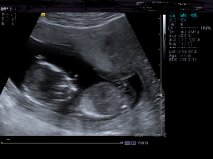

pics are really small any chance of making them bigger, i see a possible nub in the middle two pics but its hard to make out the full extent of it at that size

from the pics up i'd lean boy but not 100%